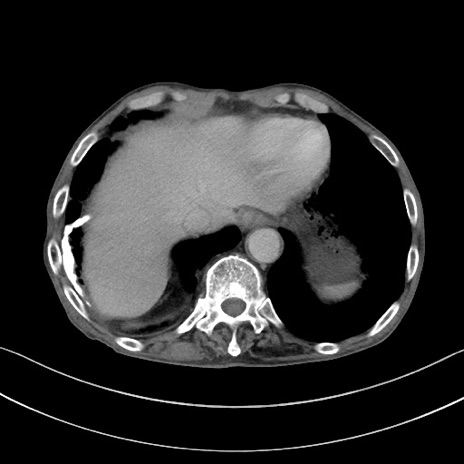

冠状断像

【症例】 70歳代男性

【主訴】右鼠径部腫瘤、疼痛

【現病歴】本日朝より上記主訴あり、受診。

【既往歴】膀胱癌にて膀胱全摘、両側尿管皮膚瘻

【データ】WBC 5600、CRP 0.56